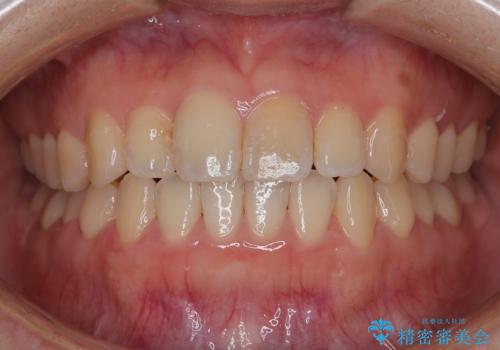

【非抜歯】インビザラインで正しい噛み合わせを

【インビザライン】がたつきをマウスピースできれいにしたい

【インビザライン】かみ合わせを整えたい